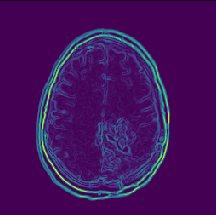

Training with the MRI dataset, which is made up of 150×\times150 gray-scale images, that is, each image is of shape (150,150,1) (Gray Scale = 1 channels). The sequential convolution feature extraction model is provided in Table 1 containing layer names, dimension, and parameters. Further, note that the CNN used in the experiment is also having the same architecture apart from the SVM classifier, which is replaced using a fully connected neural network. An example of the features extracted using a particular convolution layer on a particular slice is given as an example in Fig. 7. The generated feature vector will be used for the feature selection phase for reducing unnecessary features. LASSO regularization is used to select the optimal set of features and remove the features that may hamper the model performance. Convolutional feature extractor provides 2,49,536 features based on the total input data which has been significantly reduced to 5,240 features after LASSO feature selection is performed.

Refer to caption

Figure 7: Features extracted from a single slice in Block-1_Conv-1 layer.